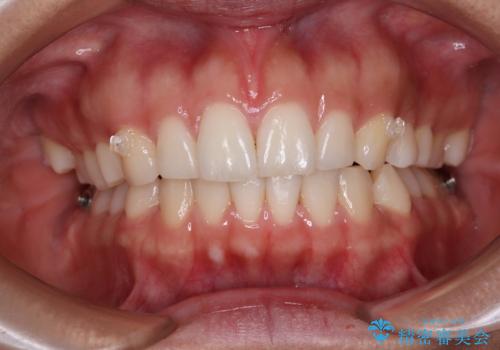

【モニター】突出した前歯 補助装置を併用したインビザライン矯正

- 上下前歯が非接触となり、前方に突出していることを気にして来院された患者様です。

咬合力が強く、全体的に歯がすり減っているため、インビザライン単独での上顎歯列移動は困難と判断し、補助装置により上顎歯列を後方移動させ、その後インビザラインにて仕上げていくこととしました。

補助装置なしでも改善できる可能性はありましたが、補助装置で確実性を上げ、短期間できっちりと仕上げることができました。